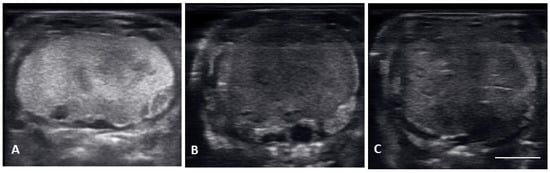

| Vitellogenic follicles (VF) | Oval shaped follicles showing a thickening hyperechoic outline as granulosa cell layer increase, hyperechoic ooplasm, and an anechoic core centrally located. |

| Preovulatory follicles (PrOV) | Elongating and increasing hyperechoic ooplasm as follicles are filled with yolk, with an elongated anechoic area located in the periphery of the ooplasm. |

| Peri-ovulatory follicles (PERI) | Elongated follicles, mostly homogenous hyperechoic structure with thick hypoechoic outline. Before female is overtly swollen. |